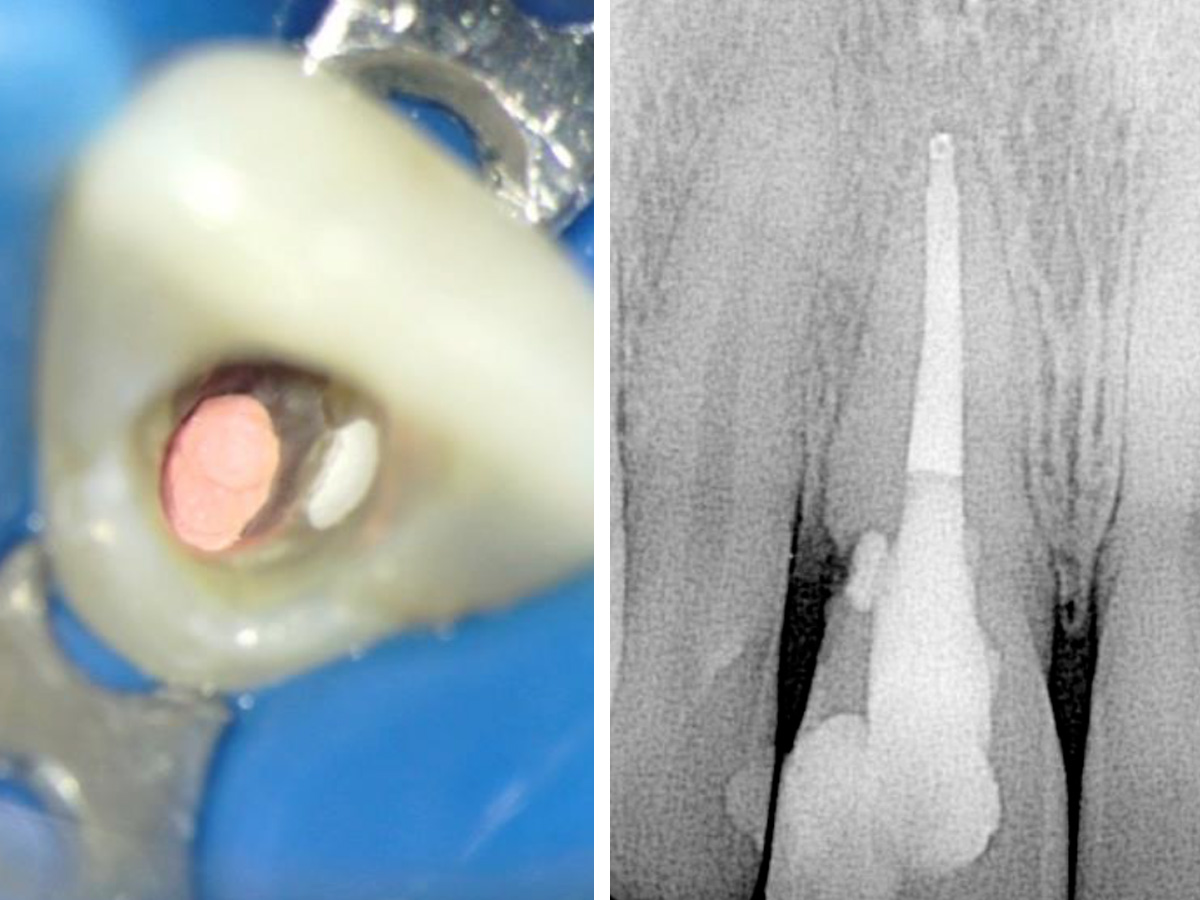

Abbildung 1

Klinische und röntgenografische Ansichten zeigen eine Fistelbildung, die bei genauerer Untersuchung zu einem distal liegenden, zervikalen Defekt an Zahn 11 führte.

Eine 29-jährige kaukasische Frau stellte sich mit Beschwerden an Zahn 11 vor, der wackelte und am Zahnfleisch Eiter aufwies. Ihre medizinische Vorgeschichte war irrelevant. Ihre zahnmedizinische Vorgeschichte beinhaltete eine Wurzelbehandlung, die 11 Jahre zurücklag. Der Zahn hatte sich etwa vier Jahre zuvor verfärbt und wurde mit Wasserstoffperoxid gebleicht. Die klinische und röntgenografische Untersuchung zeigte eine Fistelöffnung, die zu einem resorptiven Defekt im zervikalen Bereich des Zahnes führte (Abb. 1).